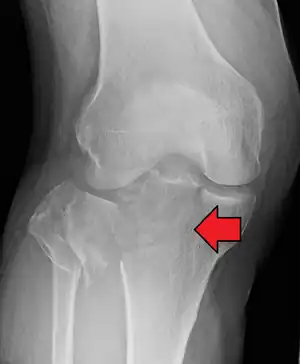

In all injuries to the tibial plateau radiographs (commonly called x-rays) are imperative. Computed tomography scans are not always necessary but are sometimes critical for evaluating degree of fracture and determining a treatment plan that would not be possible with plain radiographs.[6] Magnetic Resonance images are the diagnositic modality of choice when meniscal, ligamentous and soft tissue injuries are suspected.[7][8] CT angiography should be considered if there is alteration of the distal pulses or concern about arterial injury.

Subtle tibial plateau fracture on an AP X ray of the knee

A tibial plateau fracture seen on X-ray